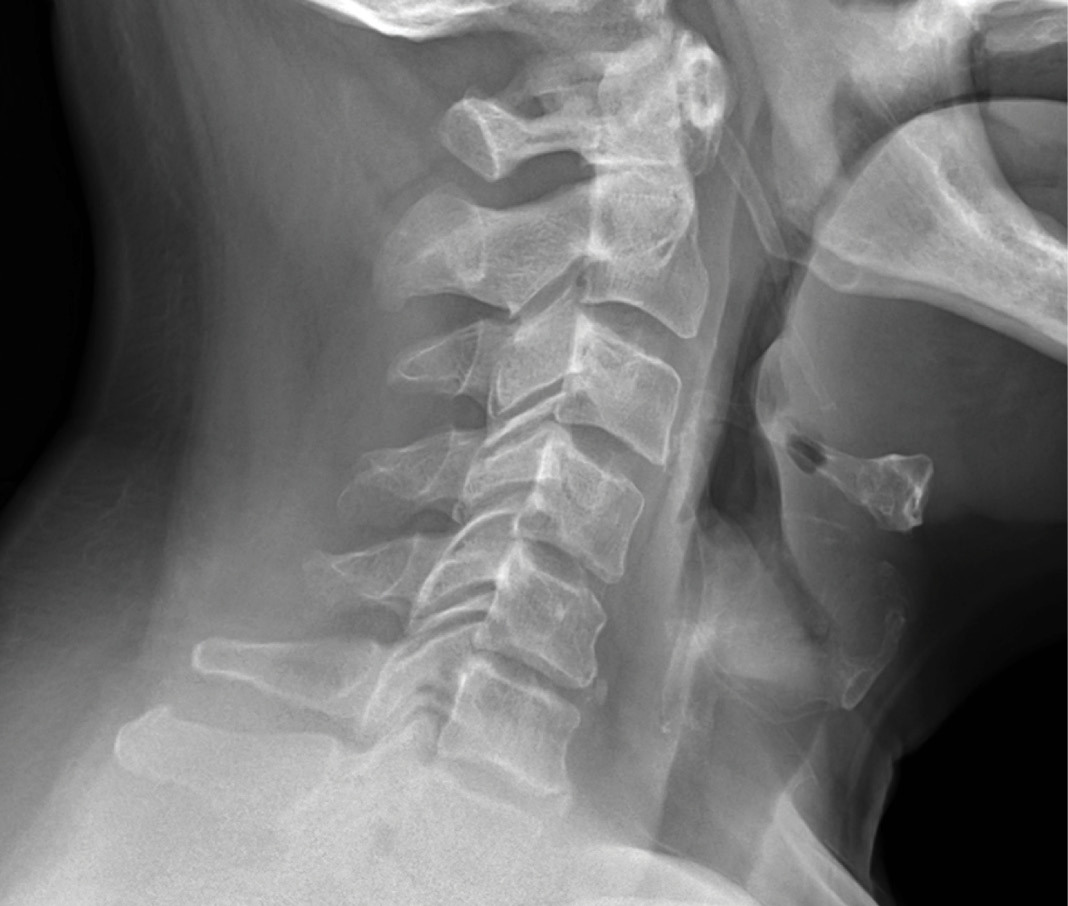

MRIs illustrated mild degenerative disc disease from C4-6 with disc herniations at both C4-5 and C5-6. The axial slice through C4-5 showed a right central disc herniation causing central and mainly right-sided foraminal stenosis. The axial slice through C5-6 showed a central disc herniation also causing central and mainly right-sided foraminal stenosis. The axial slice through C6-7 showed a left-sided disc herniation causing some left-sided foraminal stenosis, however, the patient did not demonstrate any left-sided symptoms.

Upon examination, the patient had good motion on flexion-extension, so fusion was not considered at all. My operative plan was to use prodisc cervical devices and replace both discs at C4-5 and C5-6, giving me the flexibility to use either a domed or flat implant.

On his last office visit, 3 months post-operatively, his arm pain was gone and his strength was improving, with only slight residual weakness. He was working with physical therapy for it. All medications used pre-operatively were already discontinued at that point.